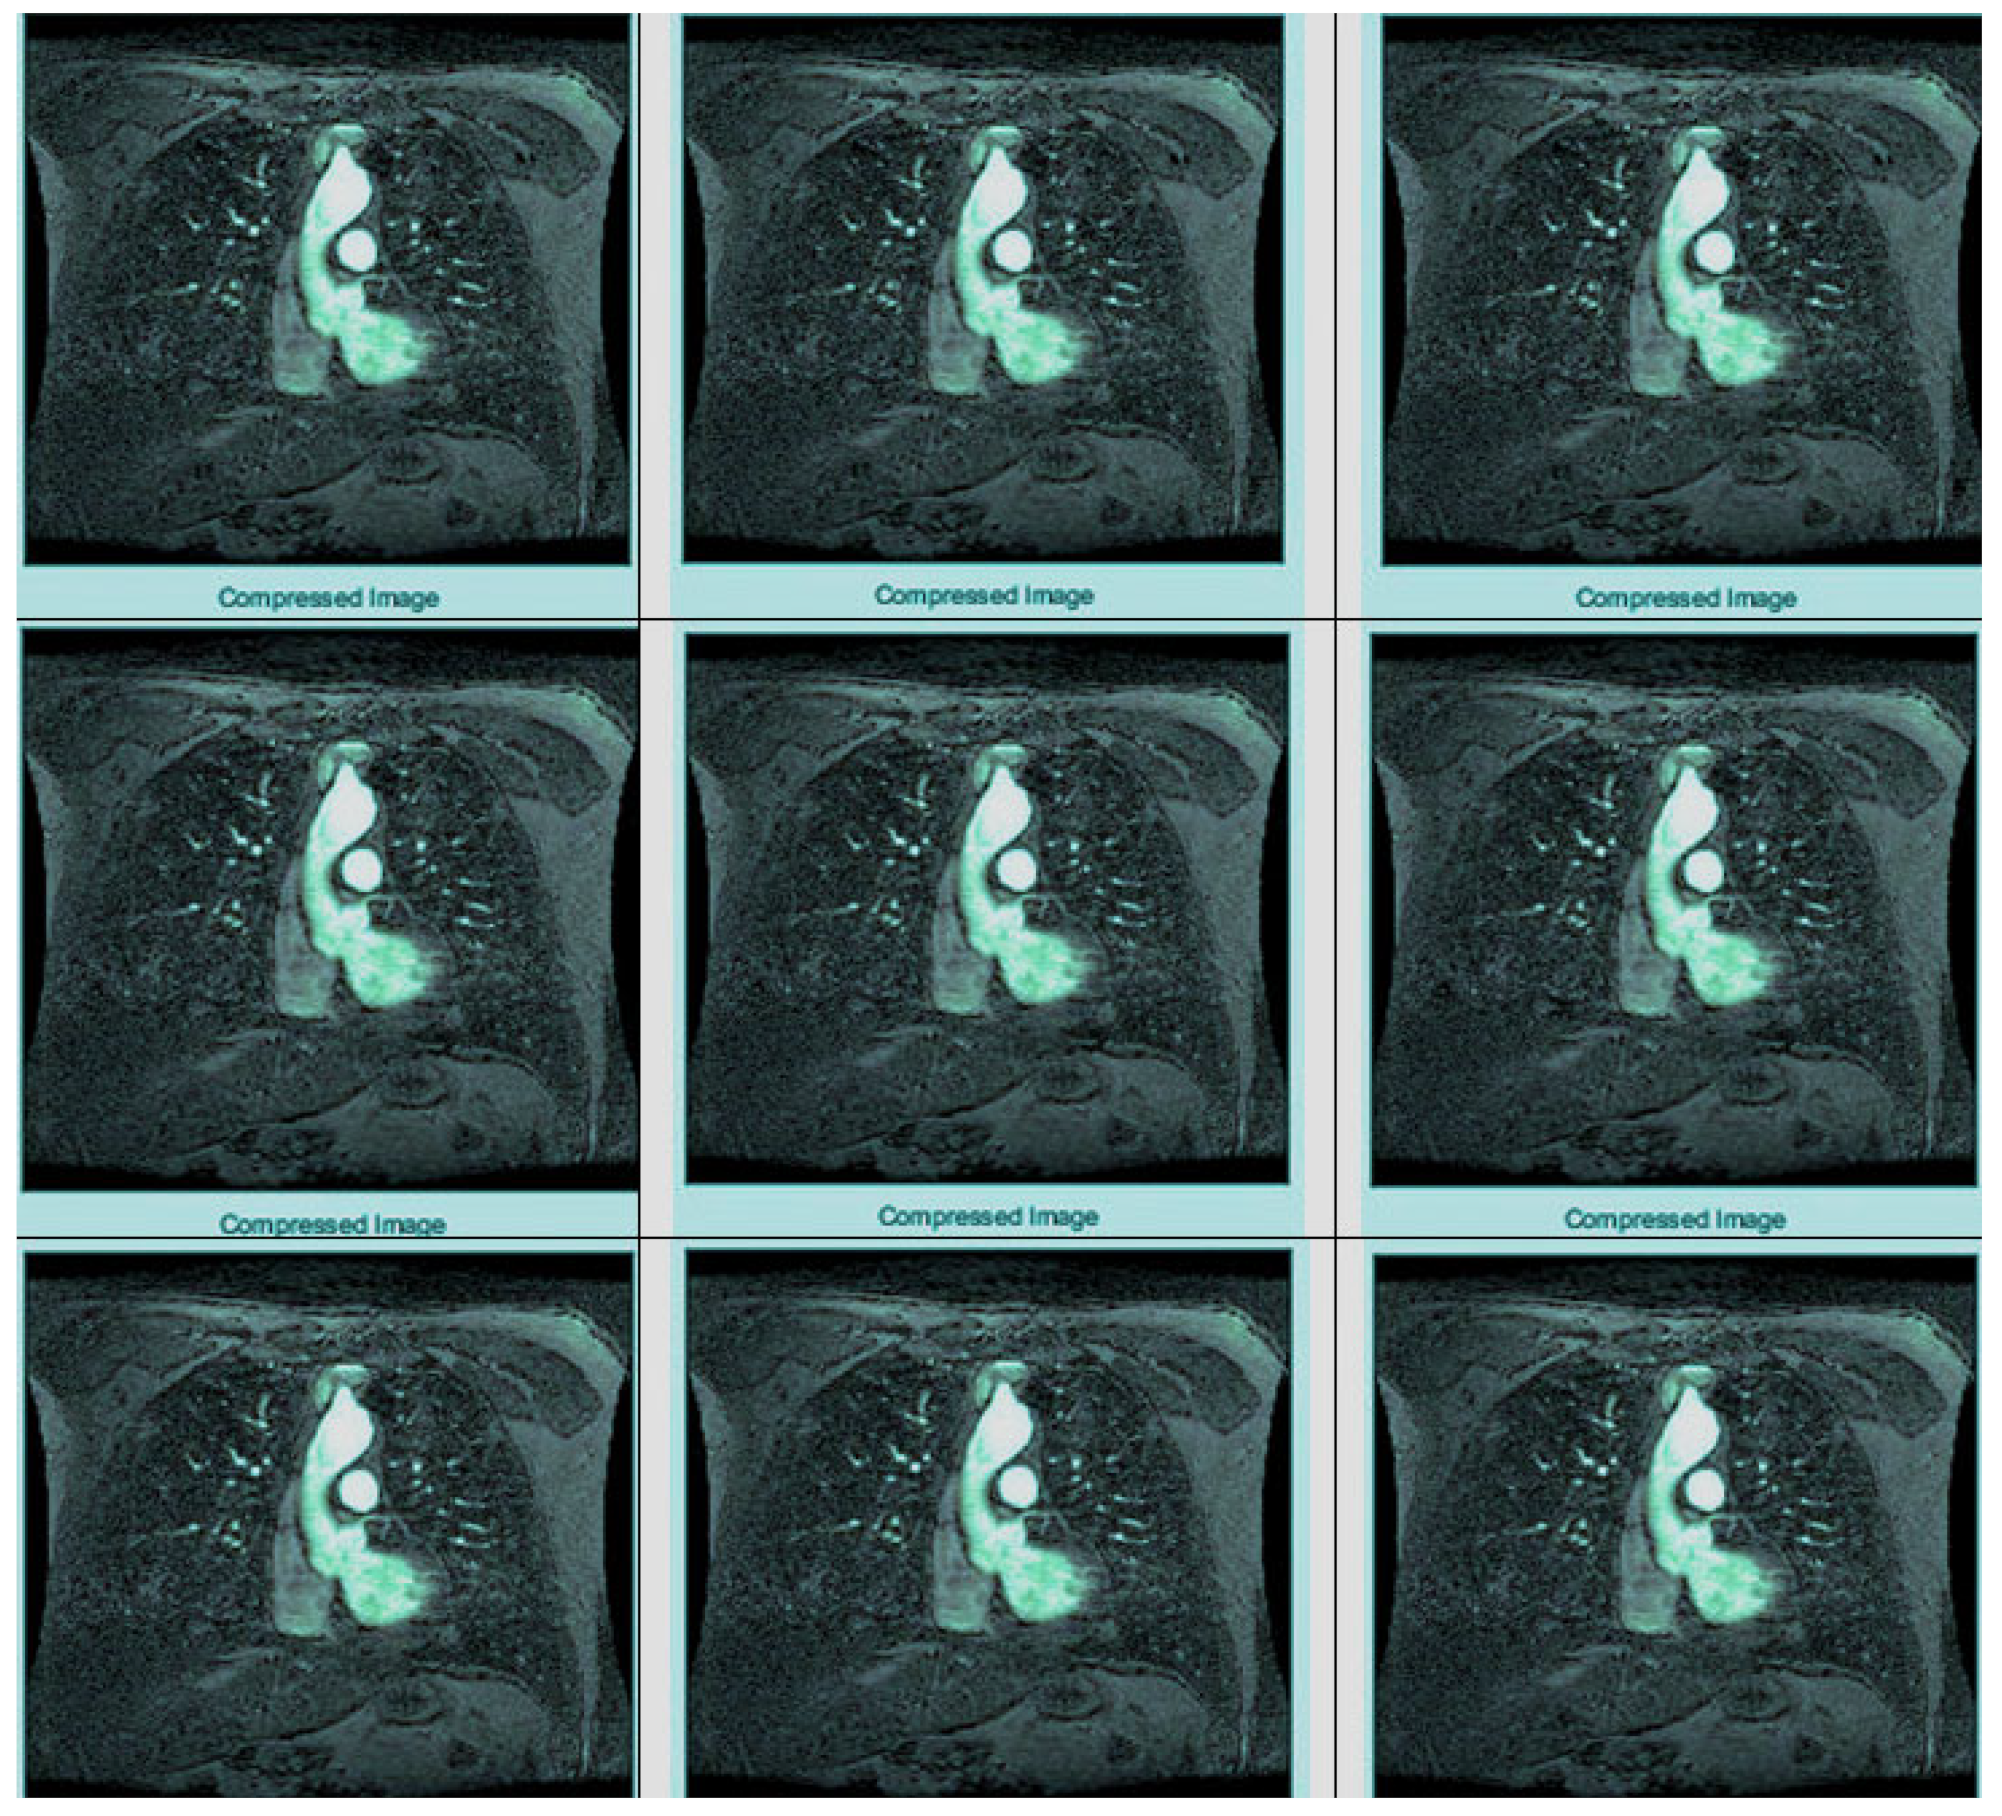

As shown in Figure 7, the complete process of wavelet photograph compresion is carried out and explored as follows. The laptop takes an entered image, before which wavelet redecoration has been finished for the digital image, thresholding has been executed on the digital picture as shown in Figure 8, and entropy coding has been completed for the photograph, all of which are essential. Wavelet compression is a technique that lets one minimize the dimensions of files at the same time as the equal time, improving them via the elimination of high-frequency noise additives. The documents can, without problems, be decreased beneath 1% of their actual length. Wavelet radically change, used to look up a sign into high-quality frequency factors at incredible choice scales, allows a picture’s spatial and frequency attributes to be concurrently revealed. In addition, competencies that could be undetected at one decision point might be easy to spot at another. One of the most vital blessings of wavelets is that they provide simultaneous localization in time and frequency areas. The most requirement in acquiring wavelets is that fast wavelet remodeling is computationally very speedy. Wavelets have the great advantage of being successful in isolating sign information. Lossless compression is more significant for programs where maintaining extraordinary files is essential. The drawback of this compression method is that it calls for massive archives to hold files after compression.

Figure 7.

Multiple compression of MRI using different wavelet families.

Figure 8.

MRI compression using core wavelet families.